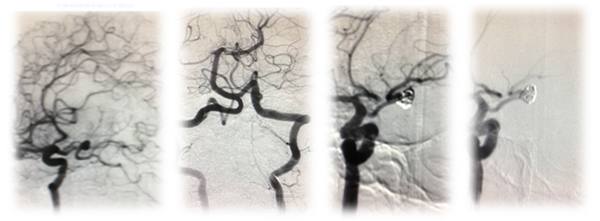

El portar un Aneurisma Cerebral es padecer una enfermedad grave; la morbi-mortalidad por rotura de un aneurisma cerebral es todavía alta. Presentamos a una paciente de 52 años de edad que sufre Ictus; evaluada clínica-radiológicamente: WFNS II Sano II Fisher III, aneurisma del sistema del complejo Posterior en su segmento P1 (2.5x 7 mm) por AngioTEM; se evaluó los dos sistemas arteriales y se optó por el mejor acceso, procedimos a la embolización con coil de desprendimiento, con buen resultado clínico y angiográfico.

Los resultados fueron tomados en cuenta basándose en la evaluación de los dos sistemas arteriales y se optó por el mejor acceso del tratamiento Endovascular; procediendo a la embolización del aneurisma a nivel de P1 por la arteria carótida interna mediante la comunicante posterior con persistencia embrionaria carótida-basilar (presencia de una arteria comunicante posterior prominente) mediante coil de desprendimiento, con buen resultado clínico y angiográfico con exclusión adecuada del aneurisma